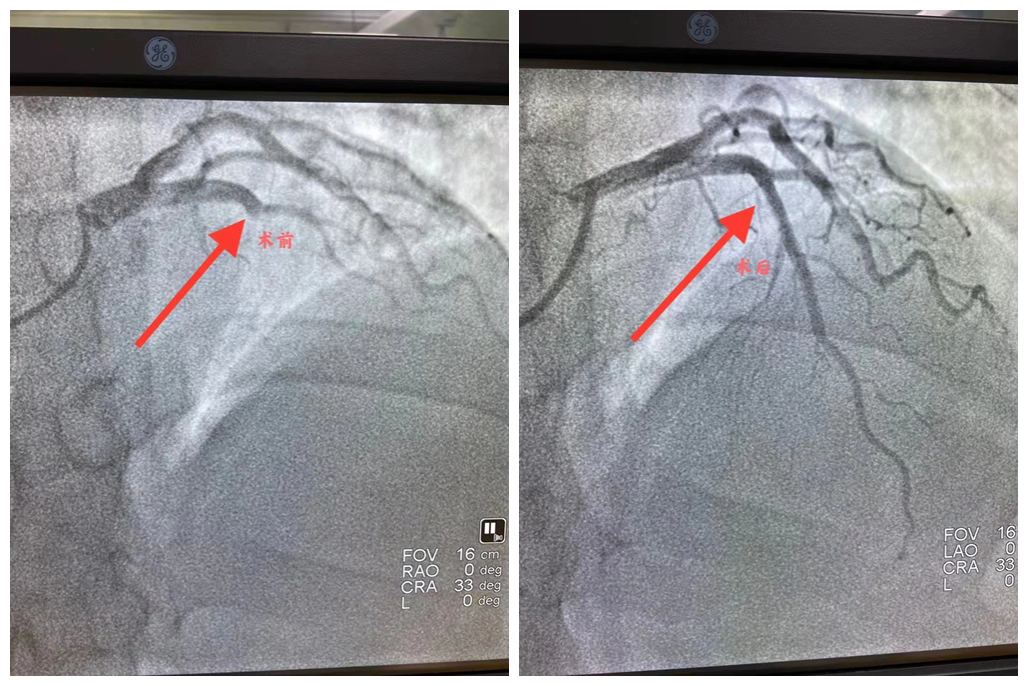

介入中心的夜晚灯火通明。患者情况与医生预判一致,前降支近段闭塞,于主任与家属沟通患者情况,经患者家属同意后,立即植入两枚支架,屏幕上呈现出了造影剂流过的黑色条带。

经过迅速有效的介入手术治疗,患者生命体征平稳,胸痛、气短症状消失。介入中心恢复了夜晚的宁静。于主任介入团队勇于担当、吃苦耐劳、一切以患者生命为中心的工作精神不断激励着科室迅速成长,一例又一例冠脉介入、射频消融、起搏器植入等手术,为秦皇岛百姓的生命健康保驾护航。